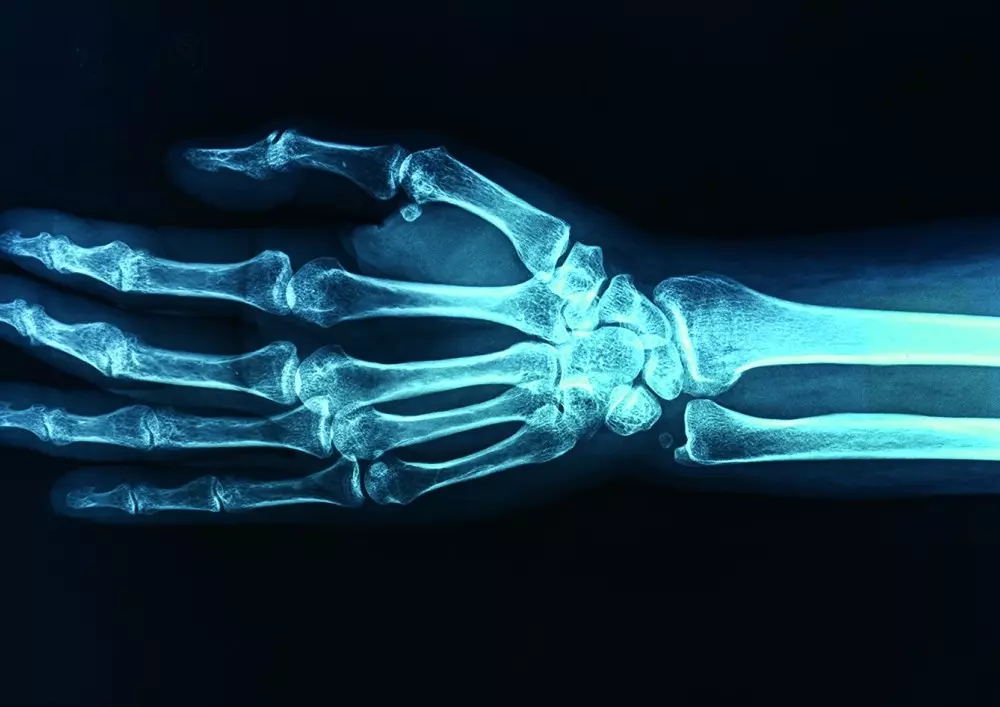

Zarostowe zapalenie stawu ramiennego

W dziale „Z praktyki gabinetu” publikujemy artykuł pt. „Postępowanie terapeutyczne w leczeniu zarostowego zapalenia stawu ramiennego”. Dr n. kf. Marcin Grześkowiak podkreśla ból i ograniczoną ruchomość stawu ramiennego, a także obniżenie możliwości funkcjonalnych wiążące się z tym schorzeniem. Zarostowe zapalenie stawu ramiennego wymaga fizjoterapii i terapii manualnej. Przedstawiamy przebieg choroby, objawy kliniczne, rozpoznanie, badanie funkcjonalne oraz planowanie terapii.